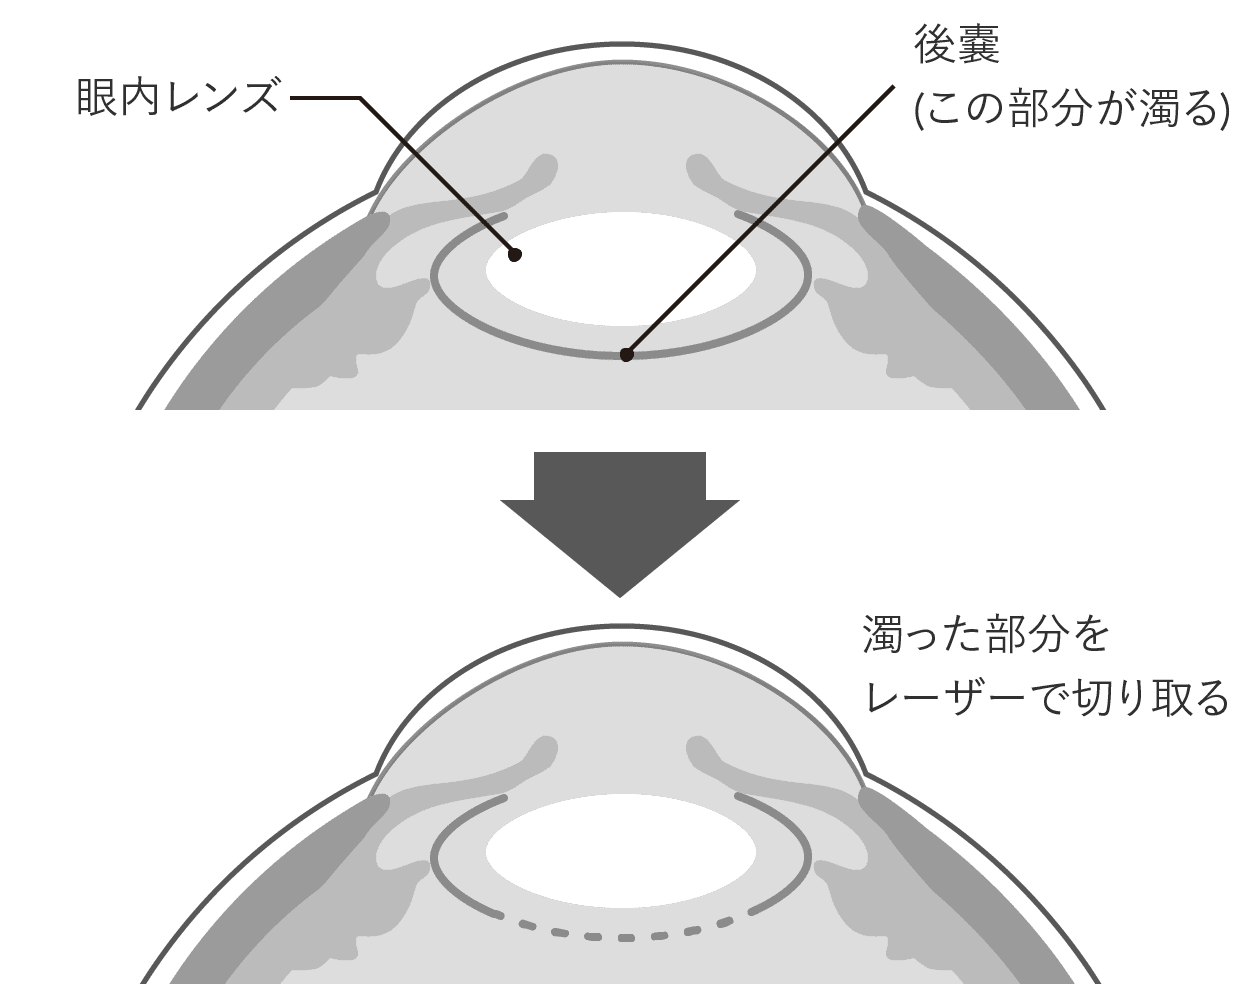

③のレーザー治療は、術後に水晶体後嚢が濁ってしまう後発白内障の場合に行います。

近年ではYAGレーザーにより切開が容易にできるため、後発白内障で失った視力はレーザー治療をすれば再び取り戻すことができます。

後発白内障は、術後1年で10人にひとり(10%)、3年後で5人にひとり(20%)、5年後では3人にひとり(30%)が発症すると言われています。

白内障手術を受けて時間が経つと、眼内レンズを入れるために残した水晶体の膜が濁ることがあります。(後発白内障)

数ヶ月から数年以降に発症することが多く、比較的よくみられる症状です。

後発白内障による視力低下は、他に原因がなければレーザー治療により回復するため心配いりません。